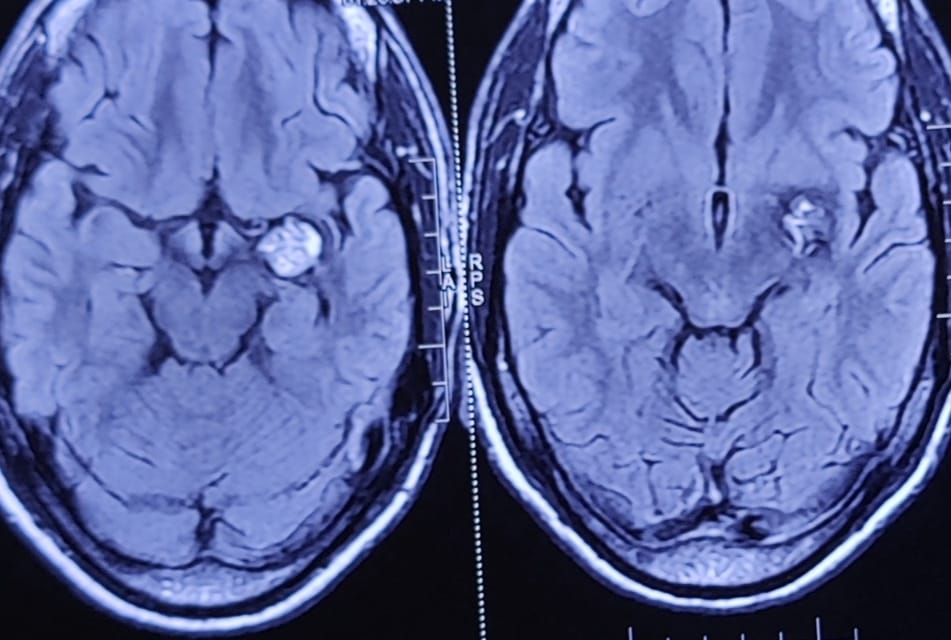

Left Medial Temporal Cavernoma

21 y/M, with recurrent severe headache and seizures, diagnosed with left medial temporal cavernoma, abutting Left MCA. And advised surgery+/- GKRS at higher center.

Patient operated 3 months back, with complete excision of cavernoma and no post operative deficits, and complete resolution of symptoms.

Repeat MRI at 3 months shows no residual lesion.